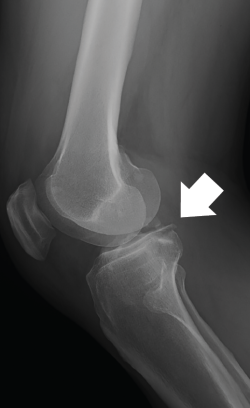

The computed tomography (CT) study evidenced a fracture of the posterior region of the internal tibial plateau with millimetric collapse and sub-centimetre avulsed fragments located immediately medial to the posterior cruciate ligament (PCL), together with a small fracture in the posterior cortical layer of the external tibial plateau without collapse, displacement or comminution (Figure 2).

Figure 2. The axial (A), sagittal (B) and coronal (C) computed tomography views show the avulsed bone fragments dependent upon the posterior root of the medial meniscus, near the insertion of the posterior cruciate ligament.